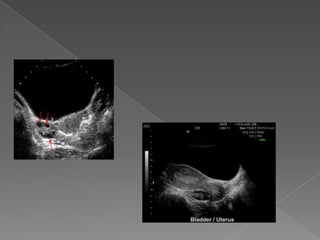

 Durante elestudio ecográfico el útero es una referencia fiable.  Localización central  Tamaño relativa/ grande  Típica forma de pera  Normal : leve desvío de línea media  Desvío marcado: masas / adherencias

• 19.

 Relación ejeuterino/ vagina  Anteversión o Retroversión  Relación cérvix / cuerpo  Anteverso flexión o retroversoflexión

• 21.

Importante en procedimientos:  Histeroscopía  Colocación de DIU  Legrado  Transferencia embrionaria  Tener en cuenta : posición según lleno vesical

• 22.

 RN ypre-púber : forma tubular Cuerpo/cuello :relación 1/1 o menor  Útero RN: 1cm mayor que la lactante  Pre-púber : 3 cm x 2 cm x 2 cm.  Adulta : 7,5 cm x 5 cm x 2,5 cm  Tamaño varia con paridad , post- parto y estabiliza con 1,5 cm de aumento.